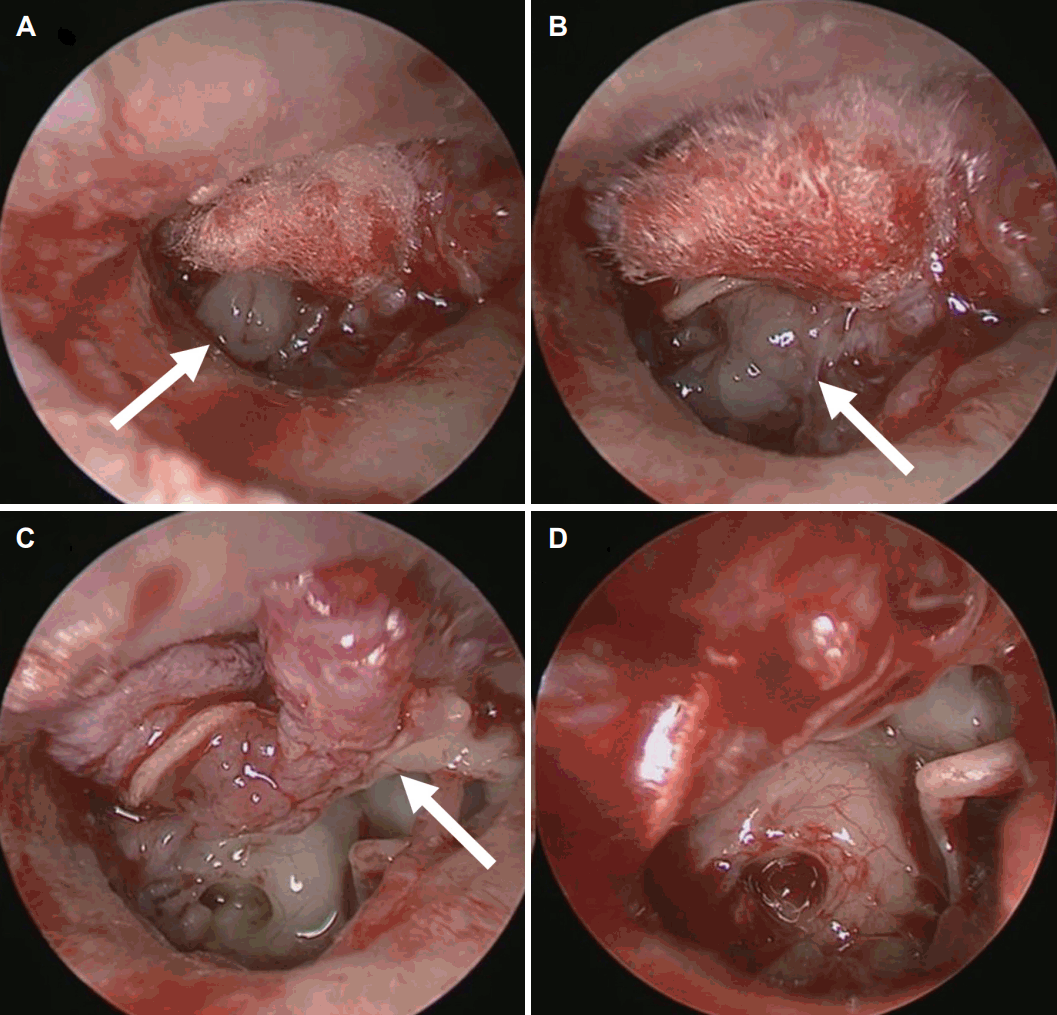

현미경을 이용하여 고막 피판을 거상하여 측두골 전산화단층촬영에서 관찰된 음영의 성상을 확인하였고, 부드러우나 염증성 육아조직처럼 쉽게 바스러지지 않으면서, 흰색의 진주종과 달리 회색을 띠는 종물이 관찰되었다. 내시경을 이용한 접근법으로 확인하였을 때 종물은 중이강을 채우고 고막의 뒷면에 들러붙은 양상을 보였다(Fig. 4). 하고실부터 종물을 제거해 나가면서 고막 뒷면에 유착된 종물도 제거하였다. 종물은 prussak’s space를 통해 상고실로 연결된 양상이었다. 종물의 성상이 전형적인 진주종의 소견이 아니었고 환자의 수술 전 좌측 청력이 정상 범주에 속하고, 이소골 연쇄는 온전한 상태로 유지되고 있어서 상고실의 병변에 대해서는 외래에서 조직검사 결과를 확인하여 치료 방향을 결정하기로 하고 고막 피판을 제자리에 위치시키고 수술을 종료하였다.

Operation findings via endoscope. A: Gray mass was noted (arrow). B: Mass was filled in middle ear cavity (arrow). C: Mass was attached to posterior wall of tympanic membrane (arrows). D: All mass was removed.